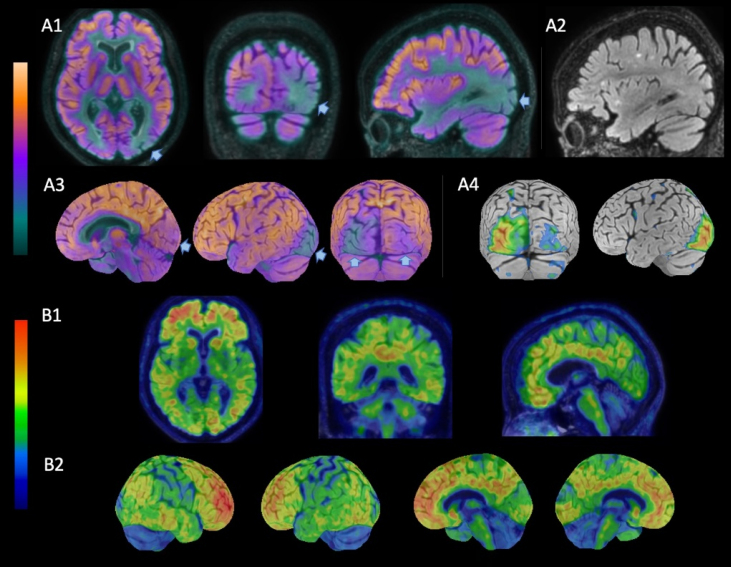

Visual field defect as the first manifestation of Alzheimer's disease.

视野缺损是阿尔茨海默病的首要表现。